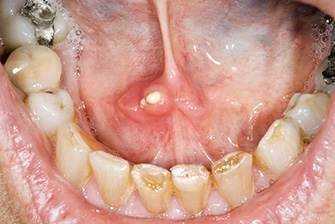

ΠΡΠΈ ΡΡΠΎΠΌΠ°ΡΠΈΡΠ΅ ΠΎΡΠ΅ΠΊΠ°Π΅Ρ, ΠΊΡΠ°ΡΠ½Π΅Π΅Ρ ΠΊΠΎΠ½ΡΠΈΠΊ ΡΠ·ΡΠΊΠ°. Π―Π·Π²ΠΎΡΠΊΠ° ΠΎΠ±ΡΡΠ½ΠΎ ΠΈΠΌΠ΅Π΅Ρ ΠΎΠΊΡΡΠ³Π»ΡΡ ΡΠΎΡΠΌΡ, ΠΌΠΎΠΆΠ΅Ρ Π±ΡΡΡ ΠΏΠΎΠΊΡΡΡΠ° Π±Π΅Π»ΡΠΌ, ΠΆΠ΅Π»ΡΠΎΠ²Π°ΡΡΠΌ ΠΈΠ»ΠΈ ΡΠ΅ΡΡΠΌ Π½Π°Π»Π΅ΡΠΎΠΌ. Π£ Π±ΠΎΠ»ΡΠ½ΠΎΠ³ΠΎ ΡΡΠΈΠ»ΠΈΠ²Π°Π΅ΡΡΡ ΡΠ»ΡΠ½ΠΎΠΎΡΠ΄Π΅Π»Π΅Π½ΠΈΠ΅, Π²ΠΎΠ·Π½ΠΈΠΊΠ°ΡΡ Π½Π΅ΠΏΡΠΈΡΡΠ½ΡΠ΅ ΠΎΡΡΡΠ΅Π½ΠΈΡ ΠΏΡΠΈ ΡΠΏΠΎΡΡΠ΅Π±Π»Π΅Π½ΠΈΠΈ ΠΊΠΈΡΠ»ΠΎΠΉ, ΡΠΎΠ»Π΅Π½ΠΎΠΉ ΠΏΠΈΡΠΈ. ΠΠ·ΠΎ ΡΡΠ° Π½Π΅ΠΏΡΠΈΡΡΠ½ΠΎ ΠΏΠ°Ρ Π½Π΅Ρ, ΡΠ°Π½ΠΊΠΈ ΠΏΡΠΈ ΠΏΠΎΠ²ΡΠ΅ΠΆΠ΄Π΅Π½ΠΈΠΈ ΠΊΡΠΎΠ²ΠΎΡΠΎΡΠ°Ρ. Π Π·Π°ΠΏΡΡΠ΅Π½Π½ΡΡ ΡΠ»ΡΡΠ°ΡΡ ΡΠ·Π²ΠΎΡΠΊΠΈ Π²ΠΎΡΠΏΠ°Π»ΡΡΡΡΡ, Π³Π½ΠΎΡΡΡΡ, Π²ΡΠ·ΡΠ²Π°Ρ ΡΡ ΡΠ΄ΡΠ΅Π½ΠΈΠ΅ ΠΎΠ±ΡΠ΅Π³ΠΎ ΡΠ°ΠΌΠΎΡΡΠ²ΡΡΠ²ΠΈΡ.

ΠΠ°Π½Π΄ΠΈΠ΄ΠΎΠ·ΠΡΠΎ Π³ΡΠΈΠ±ΠΊΠΎΠ²ΠΎΠ΅ Π·Π°Π±ΠΎΠ»Π΅Π²Π°Π½ΠΈΠ΅, ΠΊΠΎΡΠΎΡΠΎΠ΅ Ρ Π°ΡΠ°ΠΊΡΠ΅ΡΠΈΠ·ΡΠ΅ΡΡΡ ΠΎΠ±ΡΠ°Π·ΠΎΠ²Π°Π½ΠΈΠ΅ΠΌ Π±Π΅Π»ΠΎΠ³ΠΎ ΡΠ²ΠΎΡΠΎΠΆΠΈΡΡΠΎΠ³ΠΎ Π½Π°Π»Π΅ΡΠ° Π² ΡΠΎΡΠΎΠ²ΠΎΠΉ ΠΏΠΎΠ»ΠΎΡΡΠΈ. ΠΠΎΠ·Π±ΡΠ΄ΠΈΡΠ΅Π»Π΅ΠΌ ΠΌΠΎΠ»ΠΎΡΠ½ΠΈΡΡ ΡΠ²Π»ΡΡΡΡΡ Π³ΡΠΈΠ±ΠΊΠΈ ΡΠΎΠ΄Π° ΠΠ°Π½Π΄ΠΈΠ΄Π°, ΡΡΠΈ ΠΏΡΠΎΡΡΠ΅ΠΉΡΠΈΠ΅ ΠΌΠΈΠΊΡΠΎΠΎΡΠ³Π°Π½ΠΈΠ·ΠΌΡ ΠΎΡΠ½ΠΎΡΡΡΡΡ ΠΊ ΡΡΠ»ΠΎΠ²Π½ΠΎ-ΠΏΠ°ΡΠΎΠ³Π΅Π½Π½ΠΎΠΉ ΠΌΠΈΠΊΡΠΎΡΠ»ΠΎΡΠ΅ ΡΠ»ΠΈΠ·ΠΈΡΡΡΡ ΠΈ Π² Π½ΠΎΡΠΌΠ΅ Π½Π΅ Π²ΡΠ·ΡΠ²Π°ΡΡ ΠΏΠΎΠ²ΡΠ΅ΠΆΠ΄Π΅Π½ΠΈΡ ΠΌΡΠ³ΠΊΠΈΡ ΡΠΊΠ°Π½Π΅ΠΉ.

ΠΡΠΈ ΠΊΠ°Π½Π΄ΠΈΠ΄ΠΎΠ·Π½ΠΎΠΌ ΡΡΠΎΠΌΠ°ΡΠΈΡΠ΅ Π½Π° ΡΠ·ΡΠΊΠ΅ ΠΈ ΡΠ»ΠΈΠ·ΠΈΡΡΡΡ ΠΎΠ±ΠΎΠ»ΠΎΡΠΊΠ°Ρ ΠΎΠ±ΡΠ°Π·ΡΡΡΡΡ Π±Π΅Π»ΡΠ΅ ΠΏΡΡΠ½Π°, ΠΏΠΎΠΊΡΡΡΡΠ΅ Π½Π°Π»Π΅ΡΠΎΠΌ. ΠΠ³ΠΎ ΠΊΠΎΠ½ΡΠΈΡΡΠ΅Π½ΡΠΈΡ Π½Π°ΠΏΠΎΠΌΠΈΠ½Π°Π΅Ρ ΡΠ²Π΅ΡΠ½ΡΠ²ΡΠ΅Π΅ΡΡ ΠΌΠΎΠ»ΠΎΠΊΠΎ. ΠΠ°ΠΊΡΠ΅ΡΠΈΠ°Π»ΡΠ½ΡΠ΅ ΠΎΡΠ»ΠΎΠΆΠ΅Π½ΠΈΡ Π»Π΅Π³ΠΊΠΎ ΡΠ½ΠΈΠΌΠ°ΡΡΡΡ, Π½Π° ΠΈΡ ΠΌΠ΅ΡΡΠ΅ ΠΎΡΡΠ°ΡΡΡΡ ΠΊΡΠΎΠ²ΠΎΡΠΎΡΠ°ΡΠΈΠ΅ ΡΠ·Π²ΠΎΡΠΊΠΈ. ΠΠΎΠ»ΡΠ½ΡΠ΅ ΠΆΠ°Π»ΡΡΡΡΡ Π½Π° Π½Π΅ΠΏΡΠΈΡΡΠ½ΡΠΉ ΠΌΠ΅ΡΠ°Π»Π»ΠΈΡΠ΅ΡΠΊΠΈΠΉ ΠΏΡΠΈΠ²ΠΊΡΡ Π²ΠΎ ΡΡΡ, Π±ΠΎΠ»Ρ, ΠΆΠΆΠ΅Π½ΠΈΠ΅ ΠΏΡΠΈ ΡΠΏΠΎΡΡΠ΅Π±Π»Π΅Π½ΠΈΠΈ ΠΏΠΈΡΠΈ. ΠΡΠΈ Ρ ΡΠΎΠ½ΠΈΡΠ΅ΡΠΊΠΎΠΌ ΡΠ΅ΡΠ΅Π½ΠΈΠΈ ΡΡΠΎΠΌΠ°ΡΠΈΡΠ° Π³ΡΠΈΠ±ΠΊΠΎΠ²Π°Ρ ΠΈΠ½ΡΠ΅ΠΊΡΠΈΡ ΠΏΡΠΎΠ½ΠΈΠΊΠ°Π΅Ρ Π² Π³ΠΎΡΡΠ°Π½Ρ, ΠΌΠΎΠΆΠ΅Ρ ΠΏΠΎΡΠ°ΠΆΠ°ΡΡ Π΄ΡΡ Π°ΡΠ΅Π»ΡΠ½ΡΠ΅ ΠΏΡΡΠΈ, ΠΏΠΈΡΠ΅Π²Π°ΡΠΈΡΠ΅Π»ΡΠ½ΡΠΉ ΡΡΠ°ΠΊΡ, ΠΌΠΎΡΠ΅ΠΏΠΎΠ»ΠΎΠ²ΡΡ ΡΠΈΡΡΠ΅ΠΌΡ.